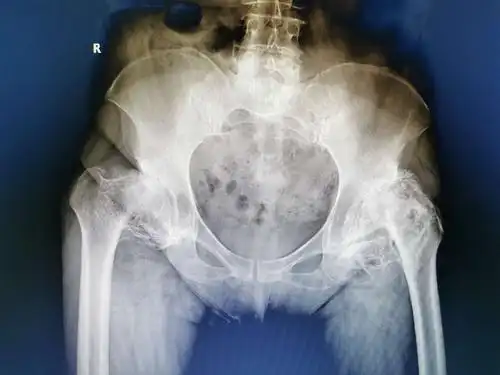

x 射线髋关节人类骨骼的骨科扫描的图像

髋关节x光照片

髋关节ct见双侧股骨头坏死